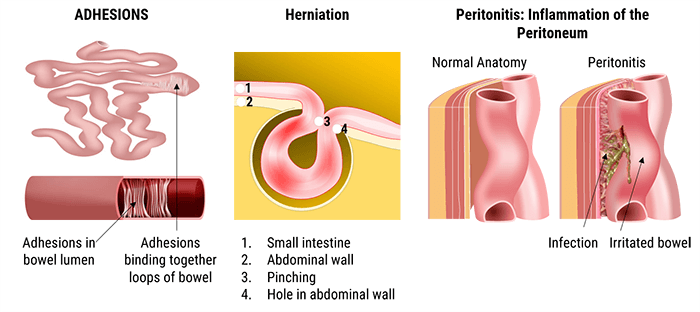

Small-Bowel obstruction is a common clinical condition that occurs secondary to mechanical or functional obstruction of the small bowel, preventing normal transit of its contents. It is a partial or complete blockage of the small intestine, which is a part of the digestive system. It is a frequent cause of hospitalization and surgical consultation and usually presents as acute abdominal pain with nausea, vomiting, bloating, and diarrhea.

Small bowel obstruction can be caused by adhesions, hernia and inflammatory bowel disorders.

Abdominal adhesions are bands of scar-like tissue that may form between abdominal tissues and organs. A hernia is an abnormal exit of the bowel, through the wall of the cavity in which it normally resides.

Peritonitis is an inflammation of the peritoneum which lines the abdominal cavity and covers the abdominal organs. According to many studies, small bowel obstructions are most often due to adhesions and hernias while large bowel obstructions are most often due to tumors and volvulus.

In general, the abdominal X-ray is used to diagnose small-bowel obstructions; however, ultrasound or MRI may be used for children and pregnant women.